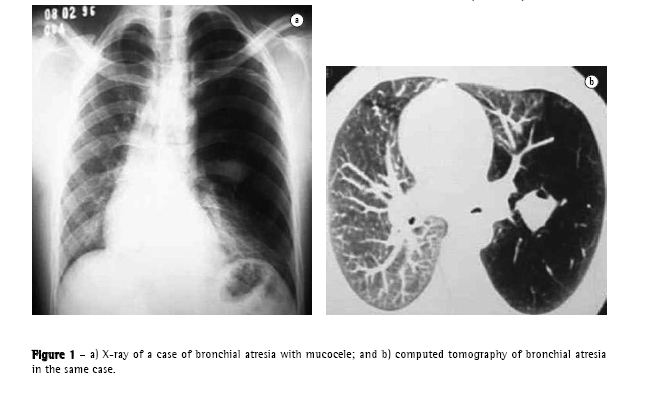

There are four principal causal mechanisms that can participate, together or in isolation, in the development of emphysema: hypoplasia (Figure 1), atrophy, hyperdistention, and partial or total destruction of the alveoli. Hypoplasia occurs due to failure in the development of the alveoli. Atrophy results from atrophy of alveolar walls, of former normal development. Hyperdistention represents distention of the alveoli beyond its normal capacity at maximum inspiration. Destruction is represented by loss of substance of alveolar walls, anatomopathologically distinct from atrophy.

In 1958,(13)a very important article waspublished, which pointed out errors in the preparation of pulmonary specimens in order to understand emphysematous lesions, describing better distention and fixation techniques. In a review of previous studies,(6) one author thus defined anatomopathological parameters, according to their distribution in relation to the lobes, (Figure 2): centrilobular, paraseptal or perilobular, panlobular and irregular.